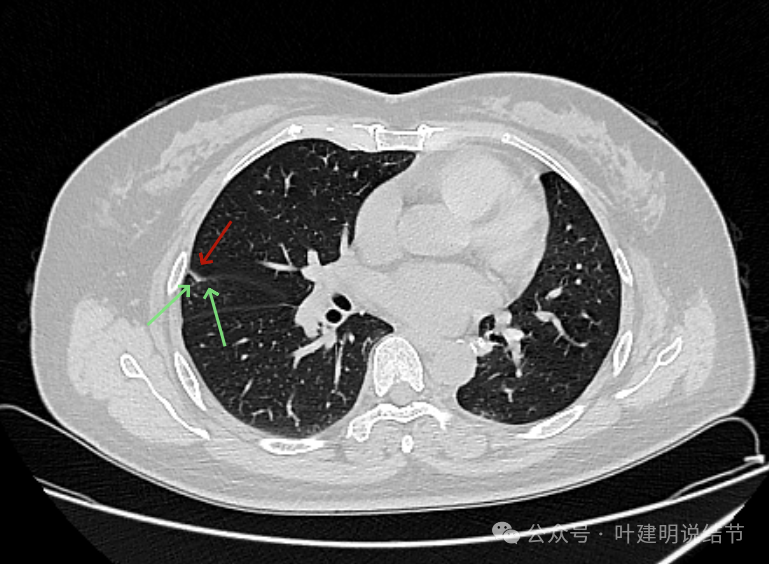

先看2024年5月时的片子:

病灶出现 ,边缘略显毛糙,有小血管进入,也见毛刺或小棘突征。

边缘不平,实性密度,贴着胸壁,胸壁处无明显增厚或胸膜反应。

表面不平,血管走向病灶。部分边缘较为平直。

此层见病灶轮廓较清,有小血管进入,表面不平,有一定的膨胀感。部分边缘较为光滑。

胸膜间隙征存在,整体边缘显得较为光滑。

似乎两个中心点,密度均是实性的。

两个中心,病灶边缘光滑,轮廓清楚。

靠着水平理解 ,病灶缺乏收缩力。

叶裂于此处略有增厚。